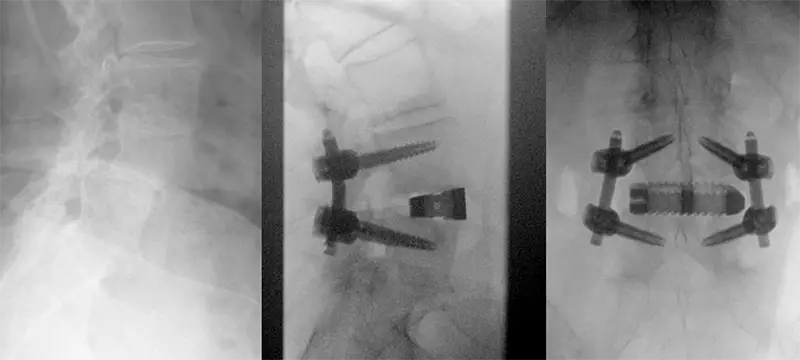

Medical image of L4-L5 spondylolisthesis treated with an interbody cage and screws.

A case of L4-L5 spondylolisthesis treated with the prone lateral approach, resulting in completed restoration of disc height and reduction of the slip.